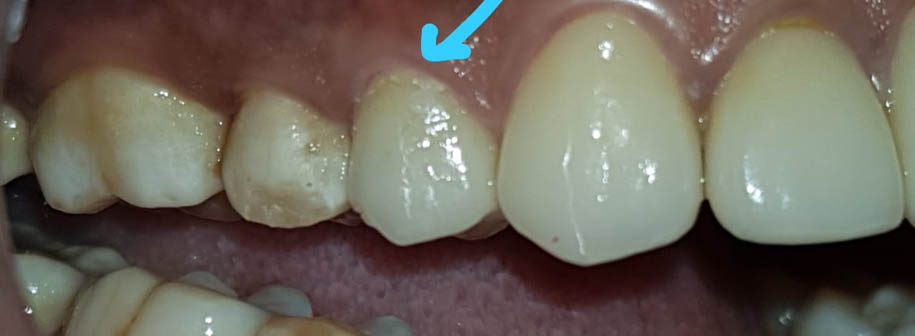

सध्याच्या आधुनिक तंत्रज्ञानाच्या युगामध्ये लोकांची आरोग्या बद्दलची जागरुकता वाढीस लागल्याचे दिसून येत आहे. यात दंत आणि मुख आरोग्याचाही अपवाद नाही .दंतवैद्यक शास्त्राला प्रगत तंत्रज्ञानाची सुयोग्य जोड मिळाल्यामुळे "दात काढून टाकणे" हा शेवटचा उपाय ठरू पाहत आहे. अगदी दहा-पंधरा वर्षांपूर्वीपर्यंत दात काढून टाकणं हाच सर्वमान्य उपाय होता परंतु आता मात्र, अगदी किडल्यामुळे दातांची फक्त मुळे जरी शिल्लक असली तरी त्यामध्ये नसे ची ट्रीटमेंट (रूट कॅनाल )करून दातांची उंची स्क्रूच्या साह्याने (पोस्ट अँड कोअर बिल्डअप )वाढवून दात पुन्हा कॅप (क्राऊन) लावून पूर्वस्थितीत आणता येतो .यानंतर गरज भासल्यास ,जेव्हा कीड हिरडीच्याही खालपर्यंत गेलेली असते (सब जिंजायवल) तेव्हा हिरडीचे छोटेसे ऑपरेशन (क्राउन लेंदनिंग )करून दाताची उंचीही वाढविता येते .या सर्व प्रक्रिया स्थानिक भुलीखाली (लोकल अनेस्थेशिया ) करता येतात .

भूल कमीत कमी किंवा अगदी न देऊनही, लेझरच्या साहाय्यानेही विना वेदना ,विना रक्तस्त्रावही हिरडीवरील उपचार करता येतात. तसेच हिरड्यांमधून रक्त , पू,येते असेल,दात ढिले झालेलं असतील तर त्या हिरड्यांवरही योग्य वेळीच योग्य उपचार (फ्लॅप सर्जरी विथ और विदाऊट बोन ग्राफ्टिंग ) करता येते . परंतु दुर्दैवाने हिरड्या खराब झाल्यामुळे किंवा खूप किडल्यामुळे दात काढूनच टाकावा लागला तर त्या जागेवर स्क्रू चे रोपण करून ( इम्प्लांट) पुन्हा पक्का दात बसविता येतो. याच पद्धतीने सर्वच्या सर्व दातही (संपूर्ण कवळीही) बसविता येते. मात्र यासाठी आधुनिक तंत्रज्ञानाची मदत घ्यावी लागत असल्यामुळे या पद्धती थोड्या खर्चिक असतात.

समोरचे दात जर किडलेले असतील तर त्यामध्ये दातांच्या रंगाचे फिलिंग (कंपोझिट) करता येते. खूपच किडलेल्या दातांना रूट कॅनाल ट्रीटमेंट करून, अगदी हुबेहूब नैसर्गिक दिसणारे सिरामिक किंवा झिरर्कॉनियम चे दातही बसविता येतात .